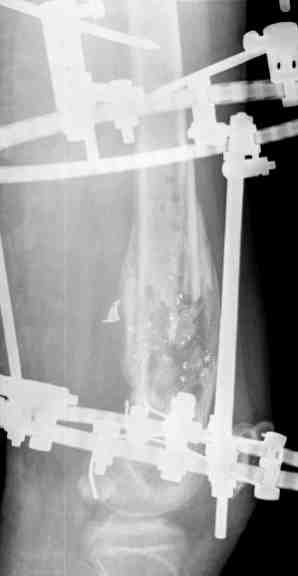

Выше представлены рентгенограммы открытого оскольчатого перелома нижней трети голени

X-rays of Compound Comminuted # Distal/3 Lt Tibia

Операционные снимки перед и после наложения аппарата Илизарова

In operation room before and after Ilizarov apparatus has been applied

Послеоперационные рентгенограммы

Postoperative X-rays

В нижнем ряду представлены рентгенограммы после окончательной репозиции.

And final reduction after Hexapod program has been finished